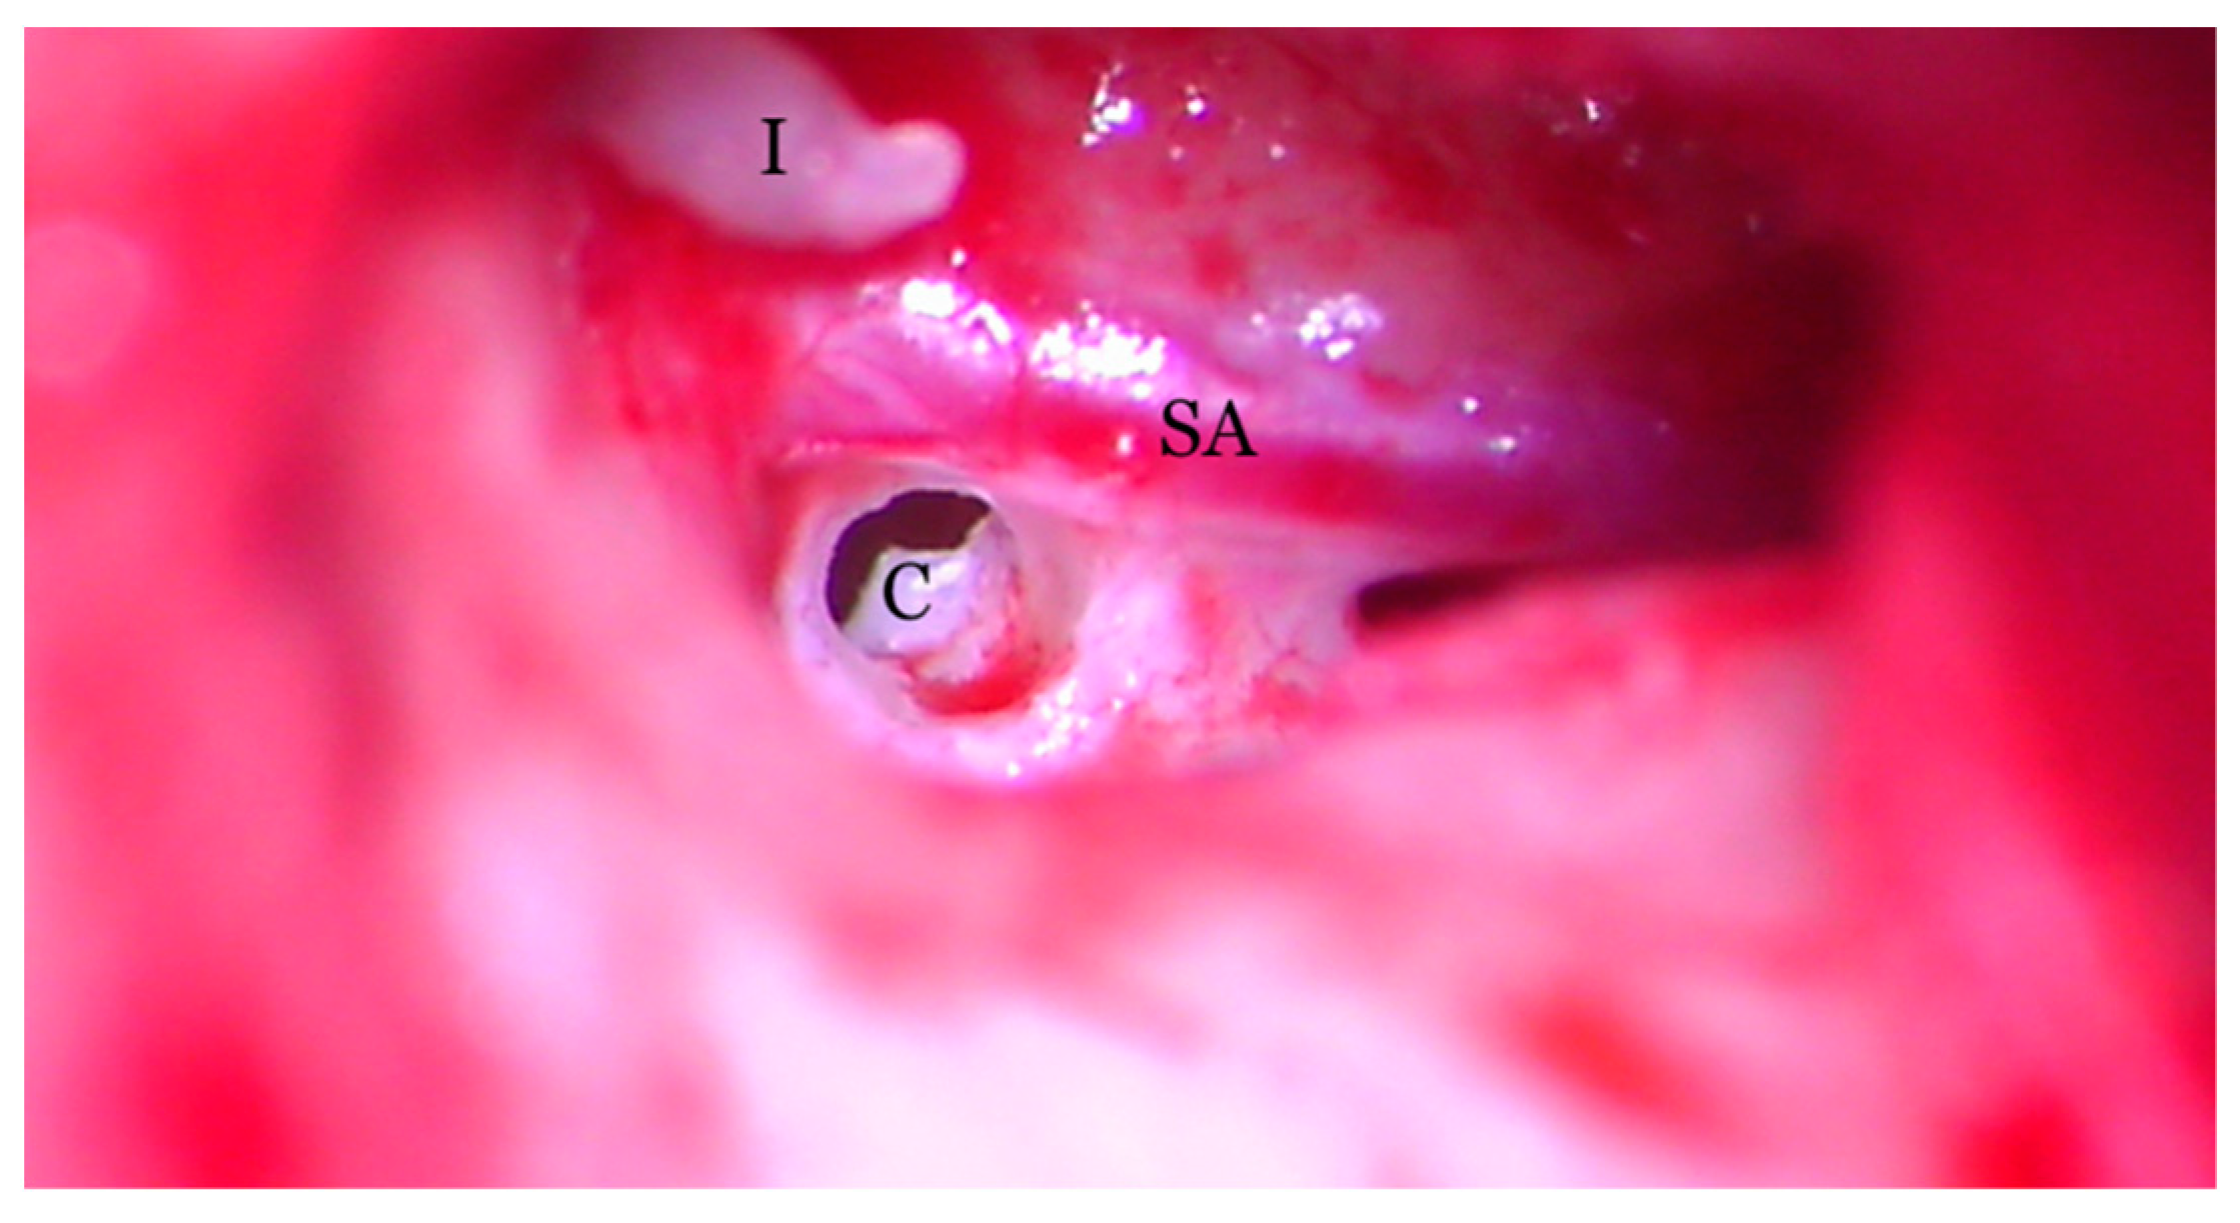

Figure 8.

Transcanalar microscopic aspect of the right middle ear: the cochleostomy (C) orifice can be observed in the near vecinity of the stapedial artery (SA) and facial nerve (FN). The long process of the incus (I) can also be observed.

Hearing loss in patient’s right ear (with PSA) was addressed by performing an ossiculoplasty with a total ossicular replacement prosthesis (TORP). After a thorough preoperative planning based on prior surgical middle ear exploration and CT imaging, a transcanalar approach to the middle ear was used. A standard tympanomeatal flap was raised and the PSA was inspected. Large dimensions, complete coverage of the oval window site and crossing over the round window niche were again noted (Figure 7). The PSA went superiorly across the promontory and entered the facial nerve canal at the level where the normal oval window niche would have been located. Successful cochleostomy was carried out with a diamond burr posteriorly to the PSA and inferiorly to the facial nerve canal. Perichondrium was used to seal the cochlea opening and also served as a support for a total replacement ossicular prosthesis (Figure 8). The TORP was seated in place and covered with a mixed graft of cartilage and perichondrium with the tympanic membrane on top of it (Figure 9 and Figure 10).